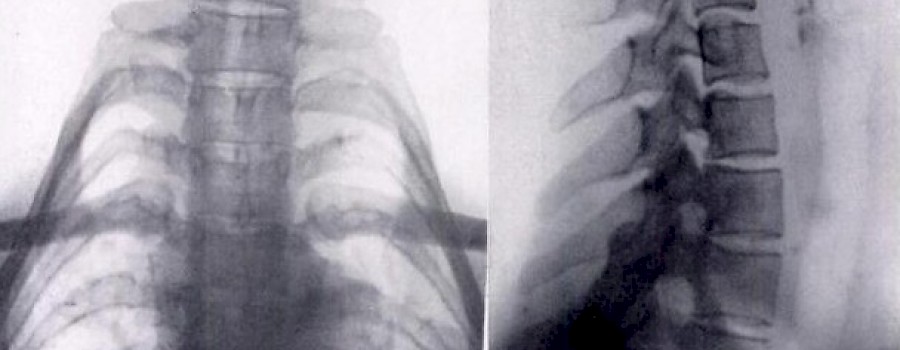

Die sogenannten "Giraffenhalsfrauen" des Padaung-Volkes tragen von Kindheit an einen schweren Halsschmuck aus Ringen, der die Schultern deformiert und den Hals scheinbar verlängert.